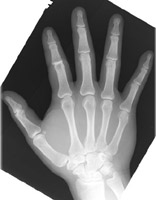

Named for injuries to baseball coaches, this term refers a dorsal dislocation of one of the proximal interphalangeal joints. Care must be made to determine if there is an associated volar plate fracture. With dorsal dislocations, the volar plate is usually detached from the middle phalanx. These injuries are due to hyperextension (such as from catching a ball). These injuries are usually managed nonoperatively, but if the collateral ligaments are disrupted, the joint will become unstable and arthroplasty will be required.

- Click on the image for a larger versionCLateral radiograph of the second digit. There is dorsal dislocation of the PIP joint. This case is unusual in that there is not an associated volar plate fracture because this is an open injury (notice the air).